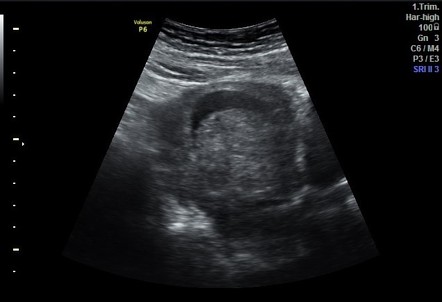

Ультразвуковое исследование при гематометре хорошо выявляет следующие анатомические признаки:

В серошкальном режиме визуализируется увеличенная матка с анэхогенным или неоднородным гипоэхогенным содержимым в её полости, соответствующим скоплению крови.

В режиме мягкотканевого сканирования определяется утолщение эндометриального слоя и деформация полости за счёт внутриматочного содержимого, с наличием эхогенных включений при частично организованной крови.

В допплеровском режиме в полости матки отсутствует кровоток, при этом может определяться повышенная перфузия по стенке при сопутствующем воспалении.

- Объём скопившейся крови в полости определяется по размеру анэхогенной или смешанной эхогенности зоны, что даёт представление о степени накопления.

- Толщина и структура эндометрия выявляются в серошкальном режиме, что помогает исключить органические причины обструкции.

- Глубина полости и её деформация точно определяются при продольном и поперечном сканировании, что позволяет оценить степень расширения.

- Однородность содержимого указывает на стадию кровоизлияния и наличие или отсутствие свежих сгустков.

- Состояние шейки матки и её проходимость может быть оценено при трансвагинальном сканировании, особенно при наличии гематометры, вызванной цервикальной обструкцией.